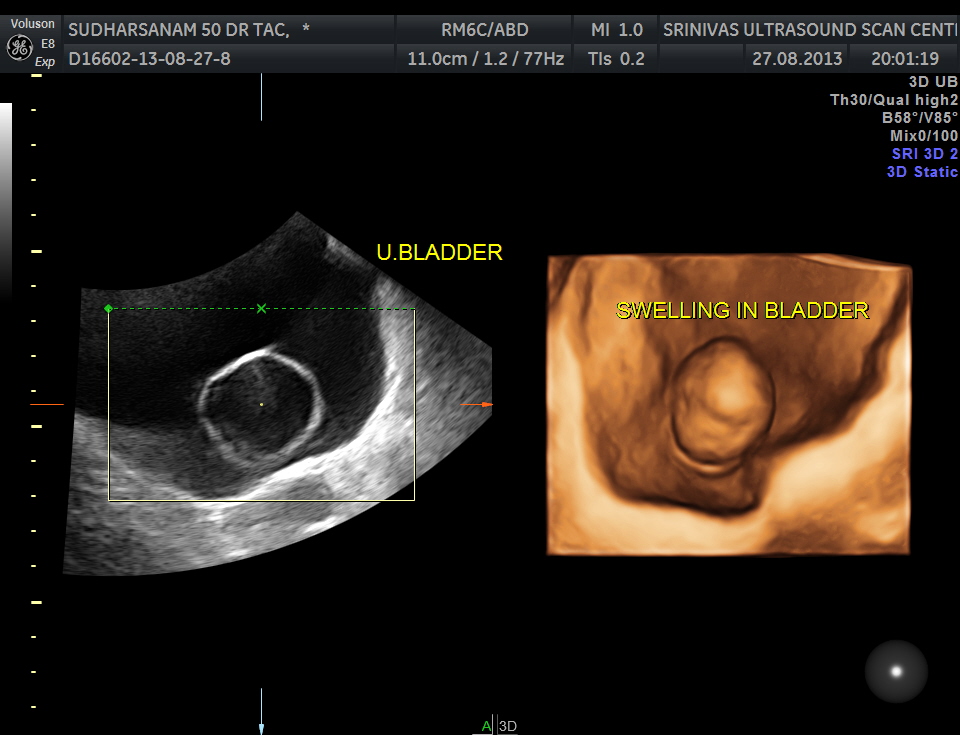

The urinary bladder showed the following :

given below are few other reconstructions

The patient was seen by the urologist and an IVP was done , which proved the diagnosis of orthotopic ureterocele . (a ureterocele entirely within the bladder.)